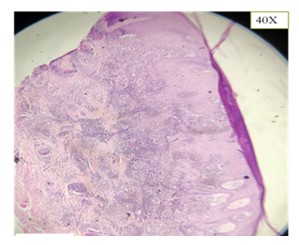

Mantoux test results were inconclusive, prompting the continuation of anti-tubercular treatment at the time. However, a biopsy was later performed since there was incomplete resolution. Histopathological examination revealed pseudoepitheliomatous hyperplasia, suppurative granulomas, neutrophilic microabscesses, lymphoplasmacytic infiltrate, occasional histiocytes, and eosinophils. Most notably, sclerotic (Medlar) bodies were observed confirming the diagnosis of chromoblastomycosis.

The patient was started on oral itraconazole 200 mg/day for 6 months, and he showed a dramatic clinical improvement following treatment. (Figure 7 & Figure 8)

Figure 7 Annular plaque with central atrophy and raised margins on left knee

Figure 8 H&E stain showing pseudoepitheliomatous hyperplasia and presence of Medlar bodies